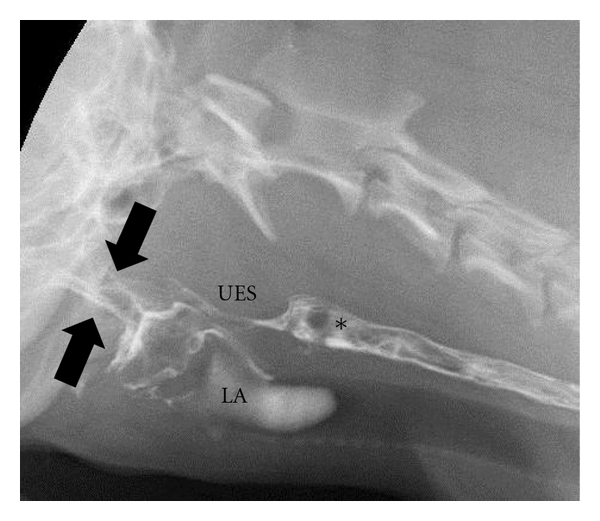

Imaging

Evaluation of Dogs and Cats with Dysphagia. Rachel E. Pollard. ISRN

Vet. Sci. 2012. Quote: The current literature is reviewed in this paper

regarding the application of diagnostic imaging in the evaluation of

swallowing disorders of the dog. The applications of radiography, contrast

radiography, and contrast videofluoroscopy are discussed with pertinent case

examples provided for emphasis. The indications for image-guided

interventions are also described. ... Figure 7: Digitally captured

fluoroscopic images are shown from a 2-year-old castrated male

Cavalier King Charles Spaniel with pharyngeal weakness related to

immune mediated polymyositis. (a) (at right here) This image is

taken as the dog laps barium that is placed into the mouth using a catheter

tipped syringe but before swallowing is initiated. A small quantity of

barium contrast medium is present in the oral cavity (black arrows) with

some residual barium in the proximal esophagus from the previous swallow

(*). Aspirated barium is also seen in the larynx (LA) and proximal trachea.

UES = upper esophageal sphincter. (b) The dorsal pharyngeal wall (DP)

contracts ventrally to meet the tongue base (TB) but bolus propulsion is

lazy and incomplete. The upper esophageal sphincter (UES) opens in a timely

manner in relation to pharyngeal contraction. (c) After the bolus passes

through the UES and the swallow is complete a moderate quantity of barium

remains in the oral cavity.